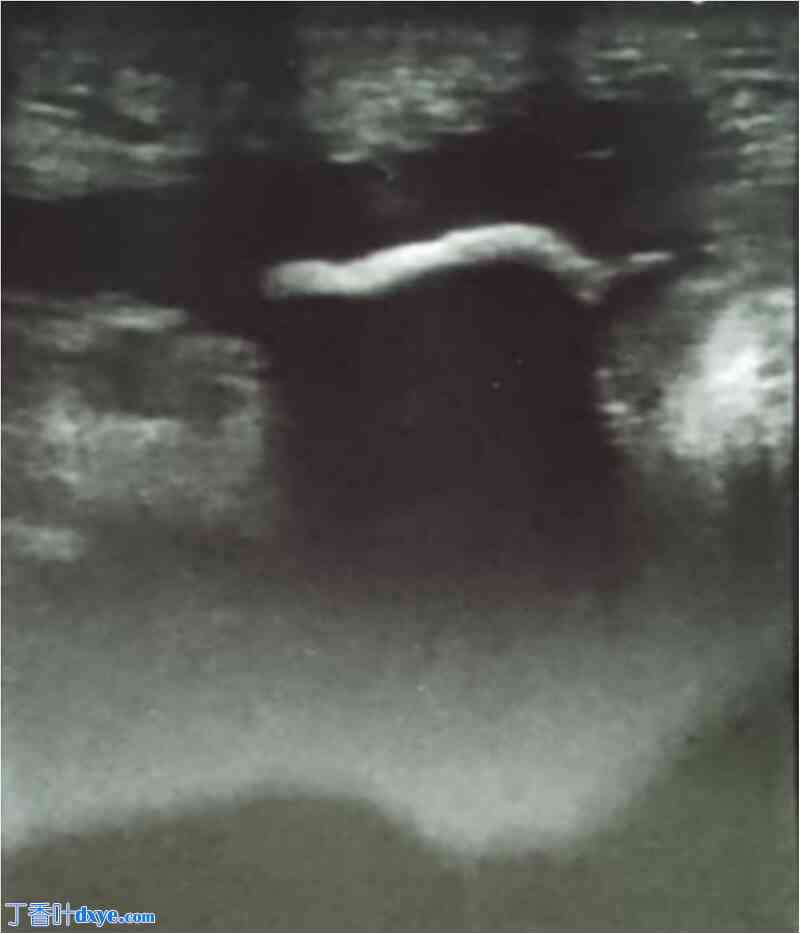

图 1.

腹部浅表超声显示瘘口处有一高回声病灶,伴有后方声影,延伸 2 cm,限制了腹腔连接处的显像。周围皮下组织可见中度 II 级水肿,未见明显的脓肿形成。